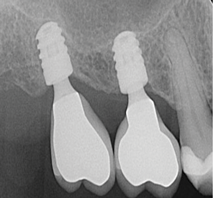

In edentulous areas with compromised bone availability in the vertical or horizontal dimensions, short and/or narrow-diameter implants are alternative treatment modalities to bone grafting procedures for conventional implant placement (Figure 1 and Figure 2). Short implants (<10 mm length) can be placed without vertical bone grafting.9,16 In general, implant width can be considered to be more crucial than implant length for the dissipation of stresses. The crestal bone area receives the maximum pressure, and very little stress is transferred to the apical portion of the implant.17 This is further reinforced through finite element analysis, which shows that implant length is not the principal factor influencing the transfer of occlusal loads to the bone-implant interface. Horizontal and vertical occlusal forces were shown to be directed primarily along the crestal bone surrounding the implant head instead of along the entire bone-implant interface.18 With short implants, there is less risk of damaging vital adjacent structures, such as the maxillary sinus, facial nerves, and roots of adjacent teeth. The relatively shallow osteotomies that accompany short implants and easier access for water irrigation also minimize the risk of bone damage from overheating.9 However, unfavorable crown-implant ratios associated with short implants can lead to complications such as marginal bone loss and even the potential loss of the implant.9 Initial implant stability can also be difficult to achieve in the posterior maxilla where very porous type 4 bone is often present.16

Fig 1. Use of short implants (6 mm length) to avoid a sinus graft augmentation.

Figure 1